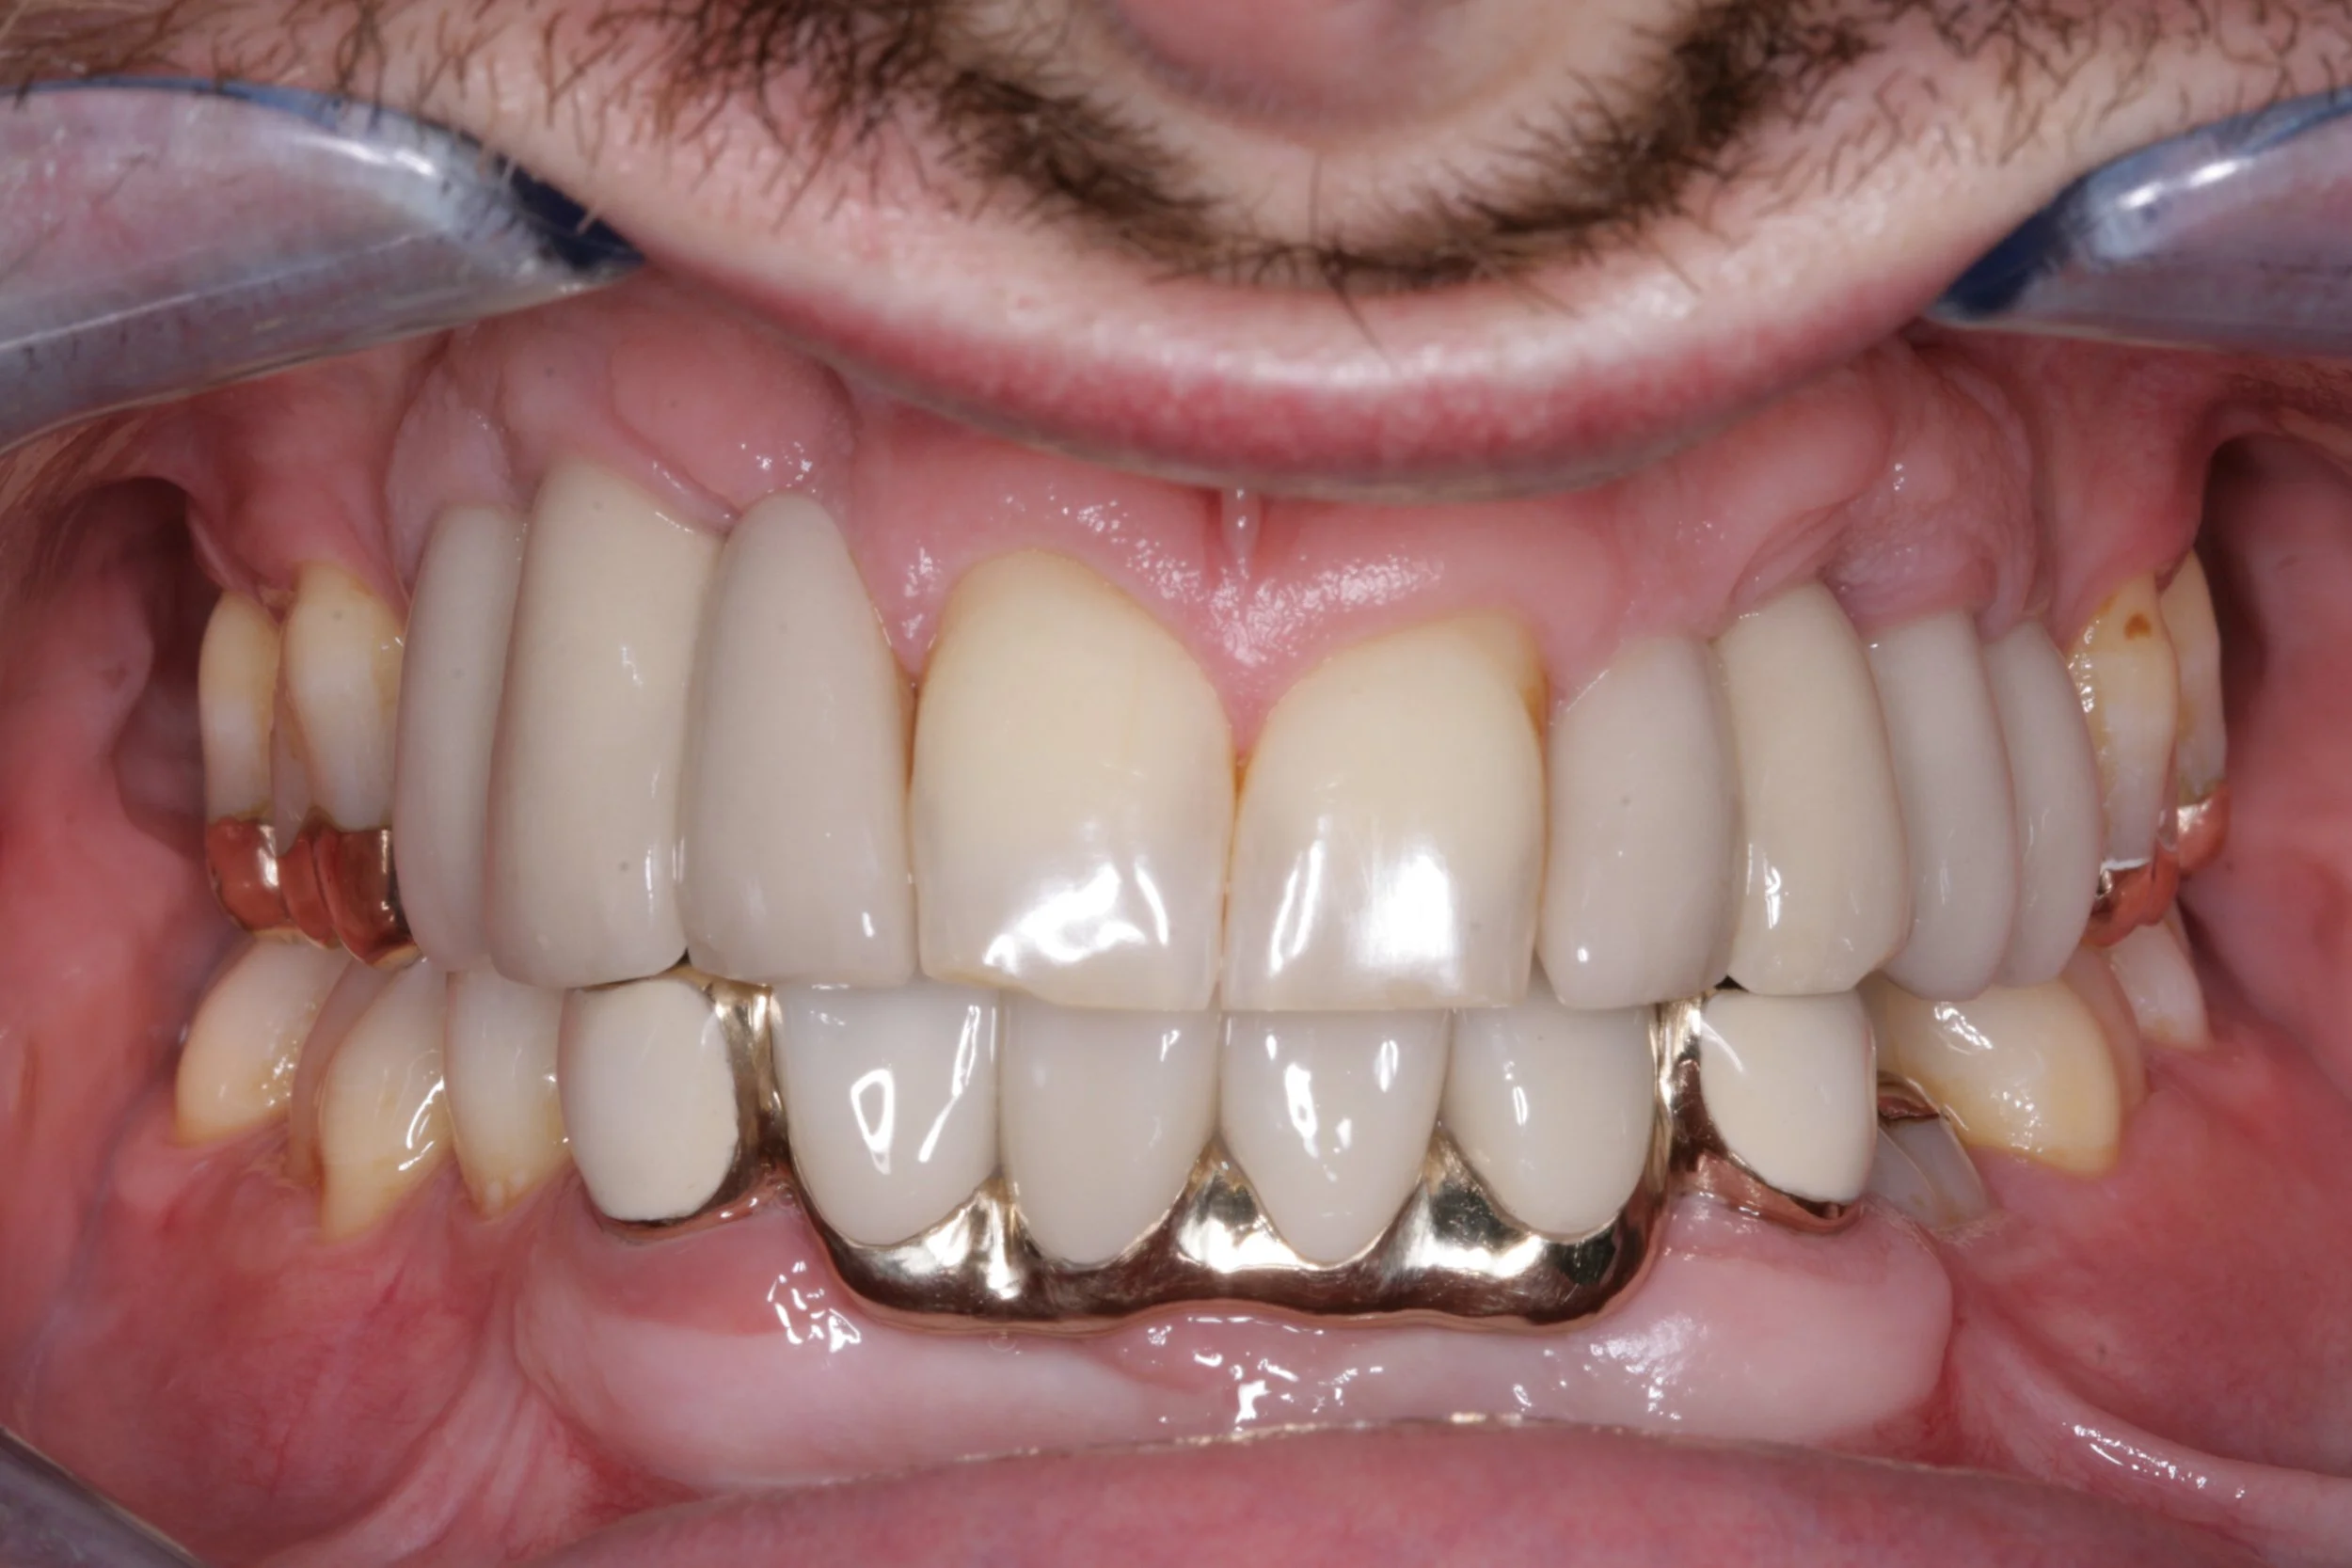

Throughout my 5 years at dental school I had bone grafts to move bone from my lower jaw to my upper jaw, placement of implants and bridges. Changes in my bite height and occlusion, eventually ditching my dentures by the age of 21.

You don’t have to be a dentist to see that my photo and x ray are different to most mouths.